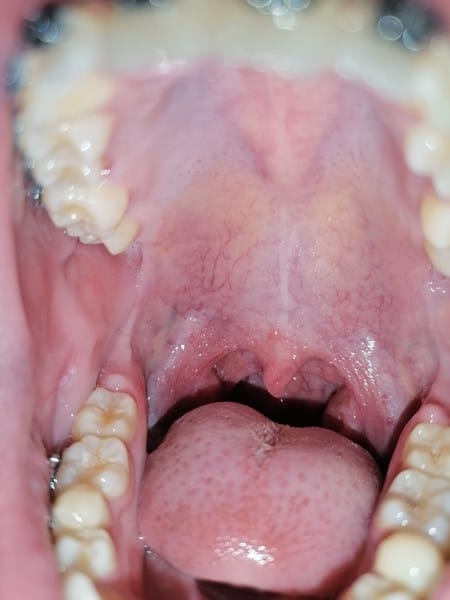

Alguien sabe a que se deba esto en mi boca?

¿Llevo días en los que mi boca a estado en muchos cambios a que se puede deber esto? Me siento preocupada